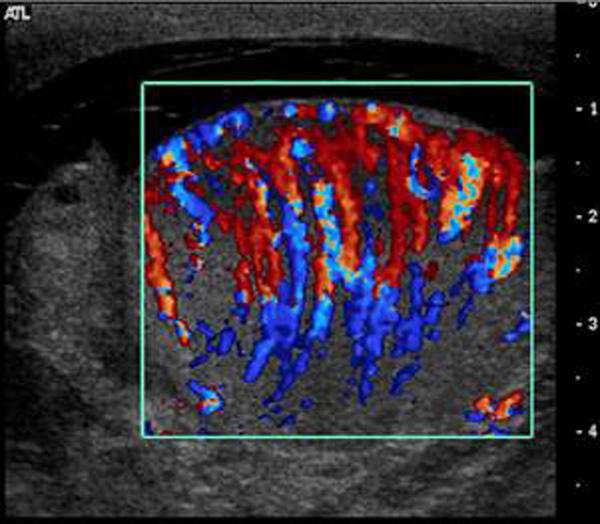

Epididymitis

inflammation of epididymis usually due to UTI

elevated WBC

Orchitis